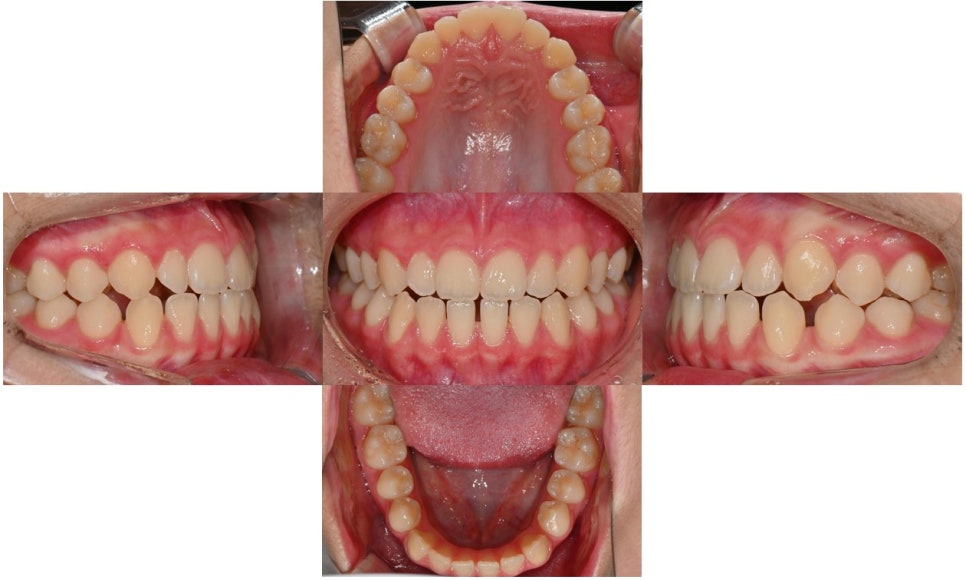

본 환자는 5년 전 페이스 마스크 장치로 1차 교정을 한 이후 앞니의 교합 상태가 다시 재발되어, 위 아래 앞니끼리 맞물린다며 2차 교정이 필요한지 상담을 받기 위해 내원하셨습니다.

2024.8.12. 초진

초진시 위아래 앞니끼리 맞물리는 절단교합 양상을 보이고 있었으며 아래 앞니는 치아 사이가 많이 벌어져 있었습니다. Cephalometric x-ray 상 아래턱이 발달한 제 3급 부정교합 (주걱턱) 양상을 보이고 있었고, 수완부사진 성장판 검사 결과 SMI 7~8단계에 해당하여 사춘기 최대 성장기는 지난 상태였습니다.

치료 전후 구내사진